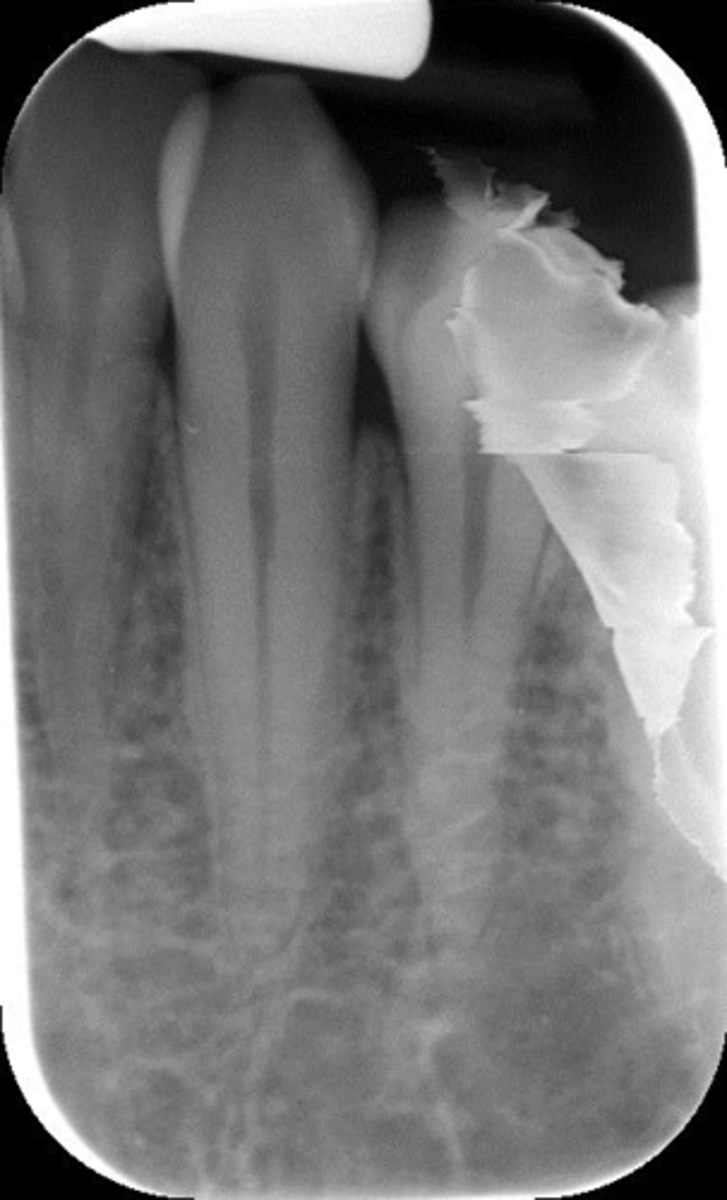

What is this error?

Damage, elongation, can't see apices